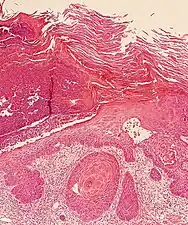

In invasive SCC, tumor cells infiltrate through the basement membrane. The infiltrate can be somewhat difficult to detect in the early stages of invasion: however, additional indicators such as full thickness epidermal atypia and the involvement of hair follicles can be used to facilitate the diagnosis. Later stages of invasion are characterized by the formation of nests of atypical tumor cells in the dermis, often with a corresponding inflammatory infiltrate.[33]

Superficially invasive squamous cell carcinoma (SCCSI). These lesions often do not show the marked pleomorphism and atypical nuclei of SCC in situ, but demonstrate early keratinocyte invasion of the dermis.[33]

High magnification demonstrates the pleomorphism of the invading keratinocytes.[33]

Invasive nests with characteristic large celled centers. Ulceration (at left) is common in invasive SCC.